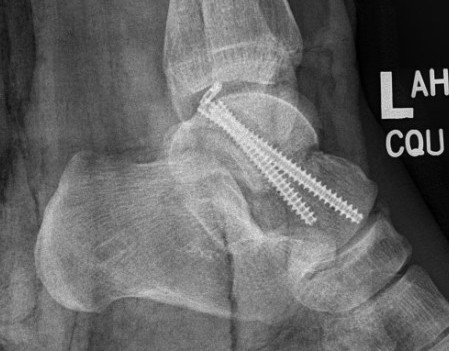

Canale view

- evaluates talar neck

- foot everted 15 deg

- look for medial shortening / varus

Cannulated screws

Xrays

| AP | Lateral | Canale View |

|---|---|---|

| Entry point of the screws |

Evaluate neck reduction

|

Evaluates the neck reduction |

Lateral off articular surface Medial through articular cartilage |

Depth of screws |

Beam angled 75o to foot Foot 15o pronated |

AP, Canale and Lateral xray